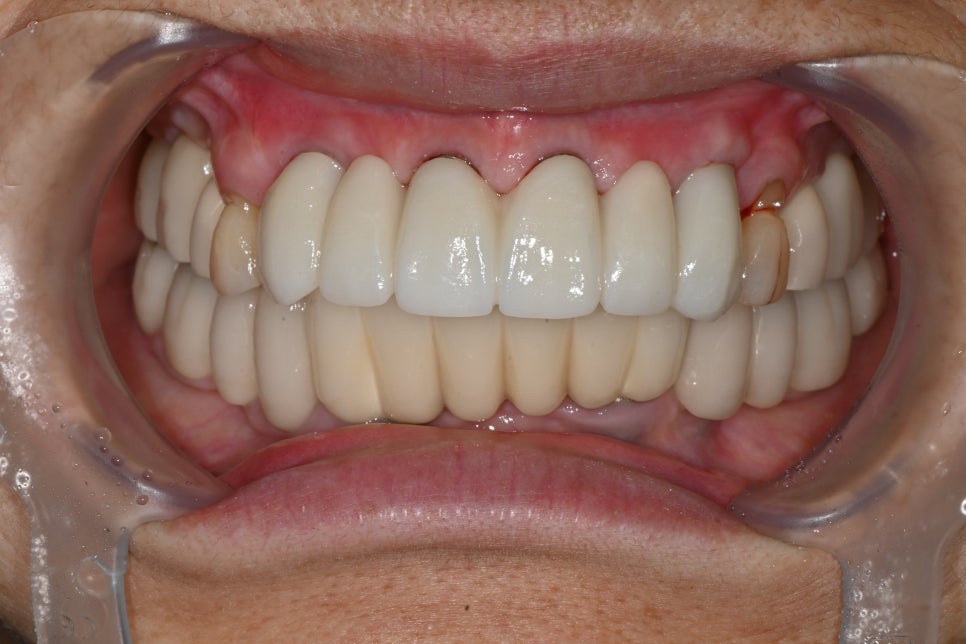

심미를 결정하는 보철 디자인

전치부 임플란트에서 가장 중요한 단계는

보철 디자인입니다.

이번 케이스에서도

맞춤형 어버트먼트 적용

임시 보철을 통한 형태 확인

최종 지르코니아 보철 제작

과정을 거쳐 완성되었습니다.

앞니는 단순히 하얀 치아가 아니라

✔ 자연스러운 색상

✔ 빛이 통과하는 투명도

✔ 잇몸과의 경계

가 모두 자연스러워야 합니다.

치료 후 변화

치료 후 환자분은을 경험하셨습니다. 특히

“내 치아처럼 자연스럽다”는 반응을 보이셨습니다.

전치부 임플란트는 단순한 치료가 아니라

이미지를 회복하는 치료입니다.

자연스러운 앞니 회복

미소 개선

발음 안정

식사 기능 회복